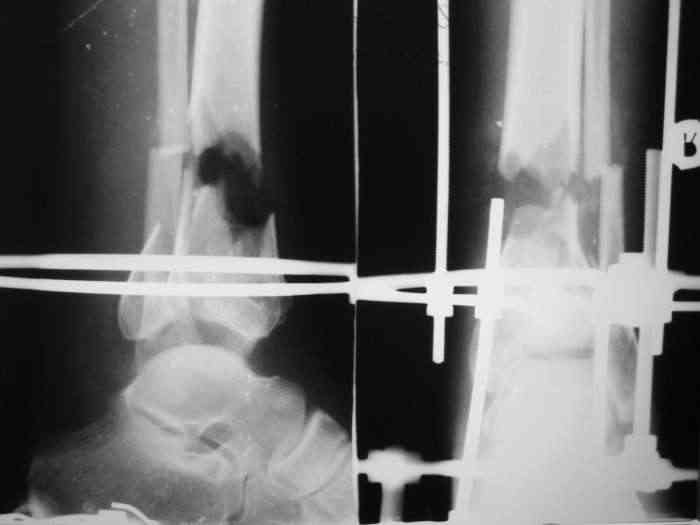

Re: Открытый вн.суставной перелом голени

При закрытой попытке поймать и собрать отломки дистального фрагмента спицами с напайками, удача покинула меня.:-(

Срепонировать суставную поверхность мне не удалось. Только зря прошил ткани, а отломки остались в прежней позиции. Так и подмывало провести спицу через ахилл ... или пойти открыто задним доступом и притянуть винтом. Но смущает один момент: на чем будет держаться резьбовая часть винта, если передная поверхность разбита в хлам? Винт будеть елозить и не даст должной копрессии. Есть ли резон, при нынешнем состоянии раны, пойти на открытую репозицию заднего отдела суставной поверхности?

Так и не определился с тактикой по закрытию дефекта. Вариант с гофрированием подразумевает резекцию малоберцовой кости на длину дефекта или "пустить" отломки вдоль, относительно друг друга, чтобы не наносить дополнительной травмы и не открываться? Вариант с рекурвационно-медиальной ангуляцией подкупает своей необычностью, но тоже, наверное, требует резекции малоберцовки, дабы не натянуть кожный покров с противоположной стороны голени. Думаю, оба варианта реальны для выполнения в наших условиях. Не нашел методики по ротационной технике замещения раневого дефекта предложенного Александром Николаевичем.